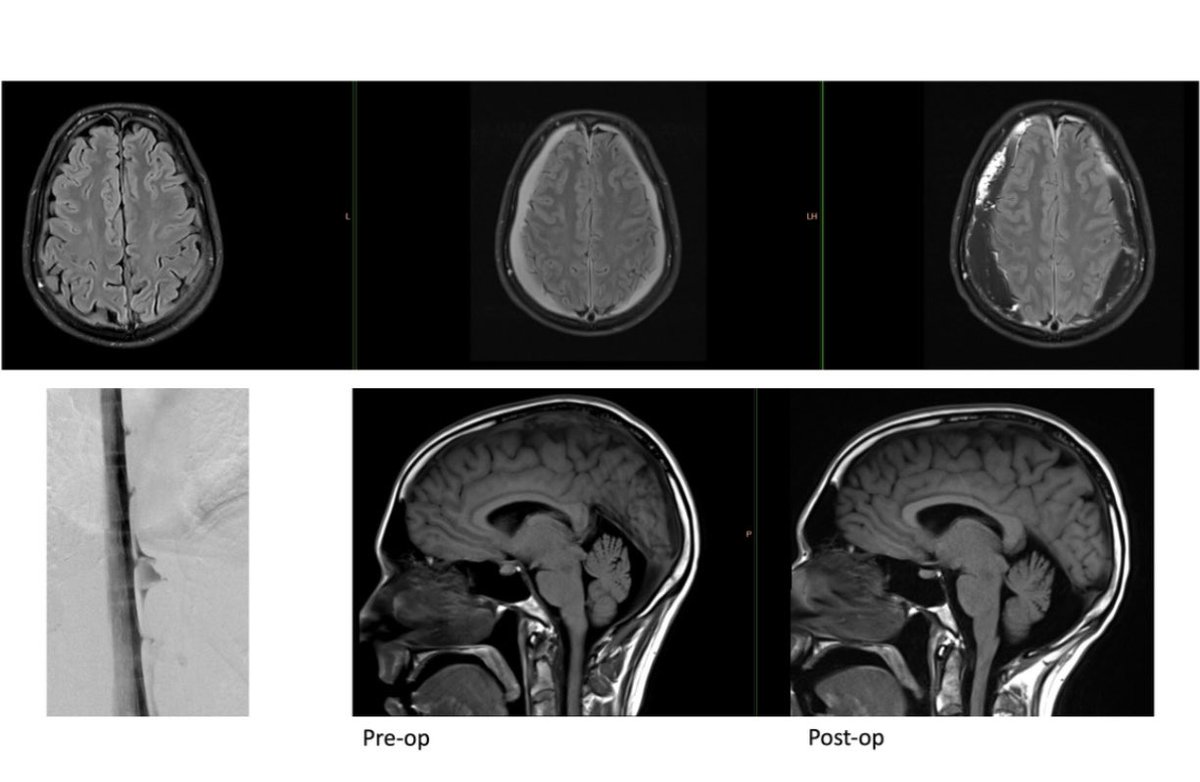

One of the very few centers in the country to offer Digital subtraction Myelography (DSM) @ApolloKarnataka for the Spinal CSF leak patients by our team @SavithKumarINR good news to our patients in India @SpinalCSFCanada @spinalCSFleak @CsfLeakIreland @csfleakinfo #SpinalCsfLeak

SharathKumarGG7's tweet image. One of the very few centers in the country to offer Digital subtraction Myelography (DSM) @ApolloKarnataka for the Spinal CSF leak patients by our team @SavithKumarINR good news to our patients in India @SpinalCSFCanada @spinalCSFleak @CsfLeakIreland @csfleakinfo #SpinalCsfLeak